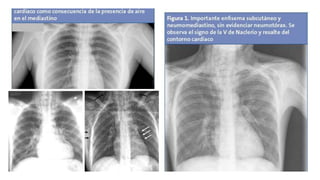

 Radiografía PA y lateral de tórax:

 Ensanchamiento mediastínico,

 Enfermedad pleural asociada focal o difusa,

 Masa de tejido blando

 Formación de burbujas de aire ectópico

(neumomediastino)

 Formación de niveles aire-líquido